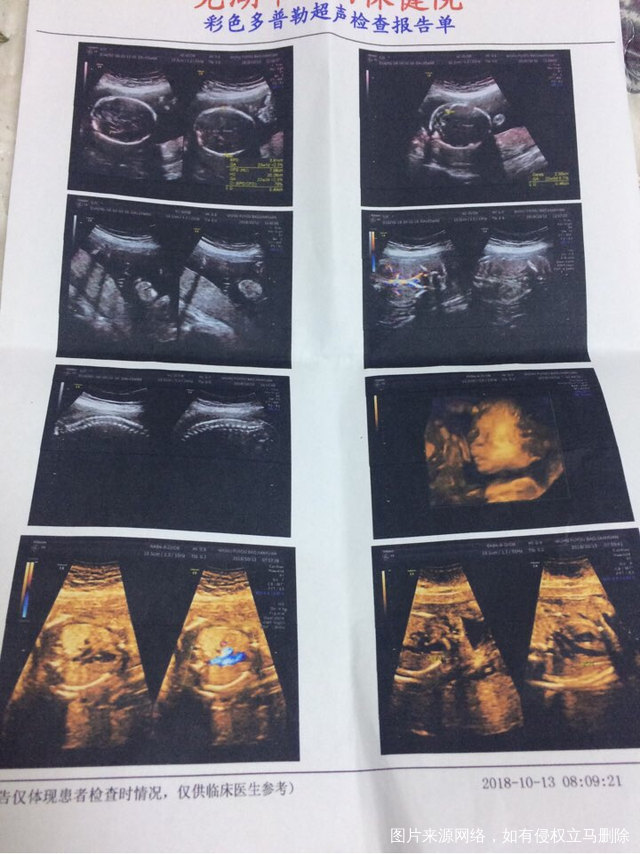

你好医生,软件显示孕周25➕,今日超23➕,28周复查b超按照哪个计算,另外b超显示三维显示左心室内见一枚强光点请问对宝宝有影响吗